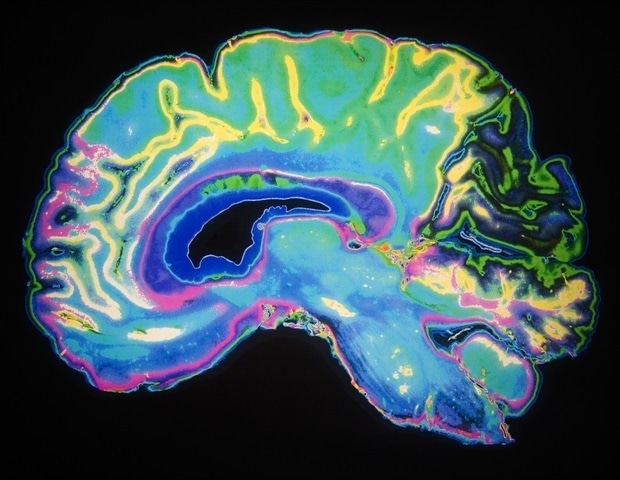

Η αυξανόμενη δημοτικότητα των ηλεκτρικών ποδηλάτων και σκούτερ στις αστικές περιοχές έχει προκαλέσει ανησυχία, καθώς οι τραυματισμοί στον εγκέφαλο και την σπονδυλική στήλη έχουν σημειώσει ανησυχητική αύξηση, όπως αποκαλύπτει νέα μελέτη. Η έρευνα, που πραγματοποιήθηκε από επιστήμονες του NYU Langone Health, διενεργήθηκε σε ένα νοσοκομείο της Νέας Υόρκης και διαπίστωσε ότι οι συγκεκριμένοι τραυματισμοί αφορούν σχεδόν το 7% των ασθενών που εισάγονται για σοβαρά τραύματα.

Η μελέτη, που δημοσιεύθηκε το 2023 στο περιοδικό Neurosurgery, εξέτασε 914 ασθενείς που είχαν υποστεί τραυματισμούς από ποδήλατα και σκούτερ κατά τη διάρκεια πέντε ετών. Από τους ασθενείς αυτούς, το ένα τρίτο παρουσίασε τραυματισμούς στον εγκέφαλο, ενώ πάνω από το 66% χρειάστηκε νοσηλεία και περίπου το 30% απαιτούσε εντατική φροντίδα. Τα στοιχεία δείχνουν ότι η συμμετοχή των συγκεκριμένων τραυματισμών στις επείγουσες περιπτώσεις του νοσοκομείου αυξήθηκε από λιγότερο από 10% το 2018 σε περισσότερο από 50% το 2023.

Σύμφωνα με τους ερευνητές, ο πιο συνηθισμένος λόγος για τους τραυματισμούς ήταν οι συγκρούσεις με αυτοκίνητα και φορτηγά, που αντιπροσωπεύουν σχεδόν το μισό των περιπτώσεων. Θλιβερός είναι ο αριθμός των αναβατών που δεν φορούσαν κράνος, με λιγότερους από έναν στους τρεις να έχουν κάνει χρήση προστασίας, γεγονός που συνδέθηκε με πολύ υψηλότερα ποσοστά τραυματισμών στον εγκέφαλο και στο πρόσωπο. Πάνω από το 20% των ασθενών βρέθηκε θετικό σε αλκοόλ, γεγονός που επίσης σχετίστηκε με πιο σοβαρές βλάβες στον εγκέφαλο.

Τέλος, οι 69 πεζοί που εξετάστηκαν στη μελέτη υπέστησαν εγκεφαλικούς τραυματισμούς σε σχεδόν διπλάσιο ποσοστό σε σύγκριση με τους αναβάτες. Οι περισσότερες συγκρούσεις καταγράφηκαν μεταξύ 6 και 8 το απόγευμα, υποδηλώνοντας ότι η κίνηση των ηλεκτρικών ποδηλάτων και οι παραγγελίες κατά την ώρα του δείπνου μπορεί να επιδρούν στην αύξηση των ατυχημάτων.

Η συγκεκριμένη μελέτη καταδεικνύει ότι οι τραυματισμοί εξαιτίας της μικροκινητικότητας προκαλούν σοβαρές βλάβες που απαιτούν νευροχειρουργική φροντίδα σε κλίμακα που δεν έχουμε δει πριν. Οι ειδικοί προτείνουν άμεσες λύσεις για την πρόληψη τραυματισμών και την καλύτερη προστασία τόσο των αναβατών όσο και των πεζών, όπως είναι η υποχρεωτική χρήση κράνους και η σχεδίαση ασφαλέστερων ποδηλατοδρόμων.